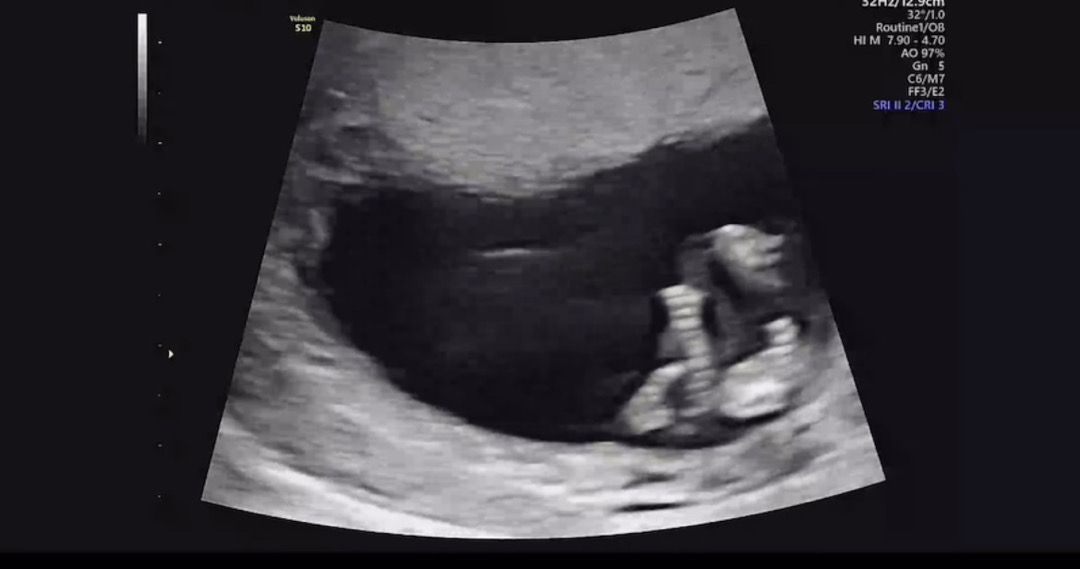

각도법 고수님 봐주세요! 11주 3일

오늘 1차 기형아 검사 받고 초음파 올려보아용 고수님들 한번 봐주세여 ❤거의 정면이에요!! 아빠다리처럼 꼬려고 하는 ..?